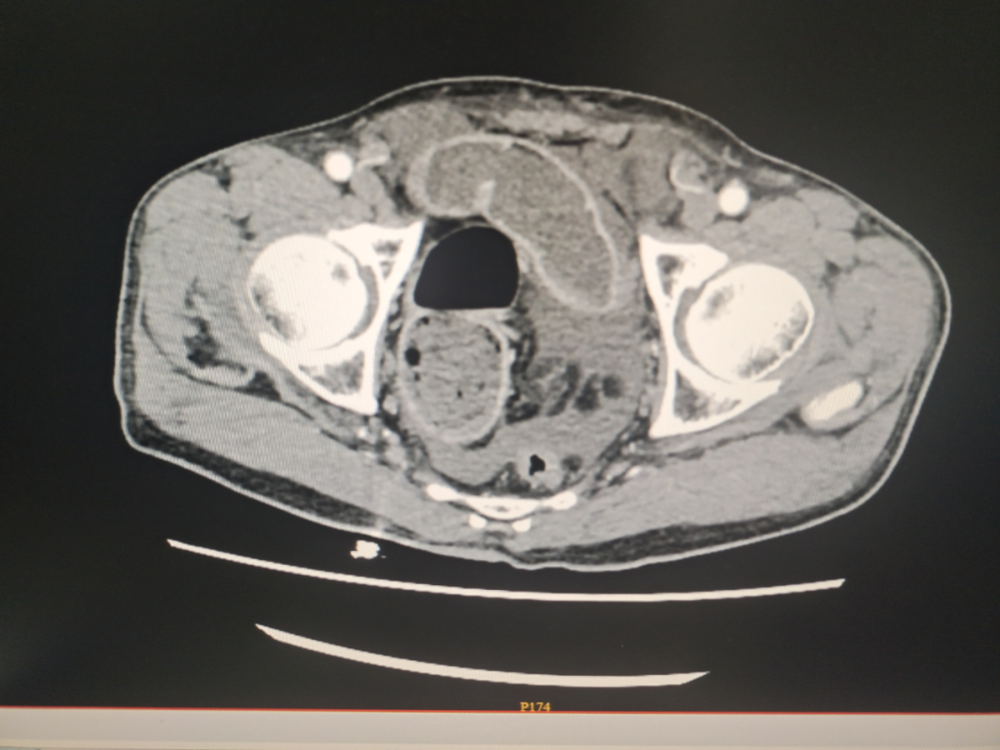

病例(lì)資料:患者,劉某某,男,73歲,因大便未解6天入院,伴有腹部脹痛(tòng),無嘔吐。入院查體;心(xīn)肺無異常、腹彭隆、壓(yā)痛、叩診呈鼓音(yīn),入院後急診腹部(bù)CT提示(shì)。乙狀結腸占位(wèi)並腸道梗阻(zǔ),急診腸鏡示:直乙交界新生物並腸道狹窄。患者於2023年11月(yuè)20日在介入室行腸鏡下腸道支架置入(rù)術,術中腸道流出糞水,術後第一天患者無腹痛(tòng)、腹脹,肛門恢複排便排氣,後複查CT示(shì)腸腔(qiāng)積(jī)氣積(jī)液明顯好轉,臨床療(liáo)效顯著。

(左)支架置入前(qián)CT

(右)支架置入後CT